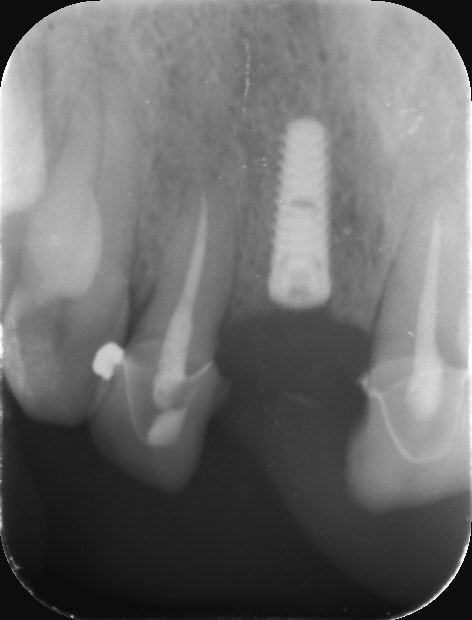

Hey ben bravo la compagnie ! C’est du propre !^^ Regardez moi voir vos bridges emax bande de vieilles branches -> ça n’a pas l’air d’être très solide.... du coup Implant plus prothèse provisoire

Un truc que j'ai remarqué, tu as plus de casse et descellement quand les 2 racines ont des valeurs mécaniques très différentes (je pense au "débattement") et là tu avais une centrale et une latérale. Les racine n'apportent pas le même soutien, ce qui doit créer des contraintes dans l'infra-structure et le matériau d'assemblage.

A la limite, quitte à faire un bridge, j'aurais rajouté la canine.